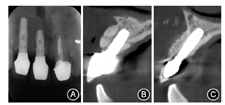

根尖X线片示12、21根充恰填,根尖周未见明显异常(图4);锥形束CT示11牙槽嵴顶宽约3 mm,骨高度约15 mm,Ⅱ类骨;12唇侧骨板完整,厚约1 mm,根尖区可利用骨高度5 mm;头颅侧位X线片示骨性Ⅰ类错

骨增量术后7个月复查,牙槽骨丰满(图9)。锥形束CT示11牙槽骨厚度8 mm,骨高度15 mm。行12、11种植手术。12残根挺松,微创拔除,探及四壁骨板完整,行11—12牙槽嵴顶切口,邻缺隙侧龈沟内切口,翻开黏骨膜瓣,11植骨区取出钛钉,定点,逐级备洞,植入种植体(Bego S 3.75 mm×10.00 mm,Semados,德国),12定点,逐级备洞,植入种植体(图10),上愈合基台,缝合;两枚种植体植入扭矩均达40 N·cm,满足即刻修复要求。于12唇侧骨板与种植体间跳跃间隙植入骨替代材料(Bio-Oss骨粉,Geistlich,瑞士),制取开窗式印模,灌注模型。